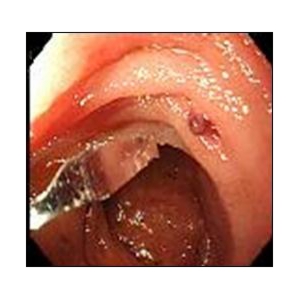

食道表在癌、早期胃癌の治療法として当科では積極的にESDを行っています。ESDとは内視鏡的に使用可能な高周波メスを使って、粘膜下層のレベルで病変を剥がし取る手技です。早期の小さな癌に対しては今までも内視鏡治療が行われてきましたが、ESDにより従来の内視鏡治療法(EMR)では切除困難であった大きな病変や、瘢痕を認める病変を一括切除できるようになりました。体を切開することなく組織も温存できるため、患者の身体的負担が少ない低侵襲医療のひとつです。

食道ESDは年間約15例、胃ESDは年間約40例ほど行っております。

《胃ESDの実際》